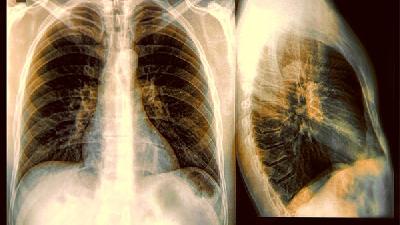

肺癌飲食注意什么?5大類食物肺癌患者不能吃

肺癌是一種治療難度非常高的疾病,要想使患者肺癌的癥狀得到有效的控制,患者一定要注意自己的日常飲食,日常的飲食當(dāng)大補(bǔ)的食物、發(fā)物、煙酒、燒烤類食物和含碘量過(guò)高的食物等等都是需要禁止服用的,這些都會(huì)是患者癌癥的病情加重。肺癌飲食注意什么?5大類食物肺癌患者不能吃